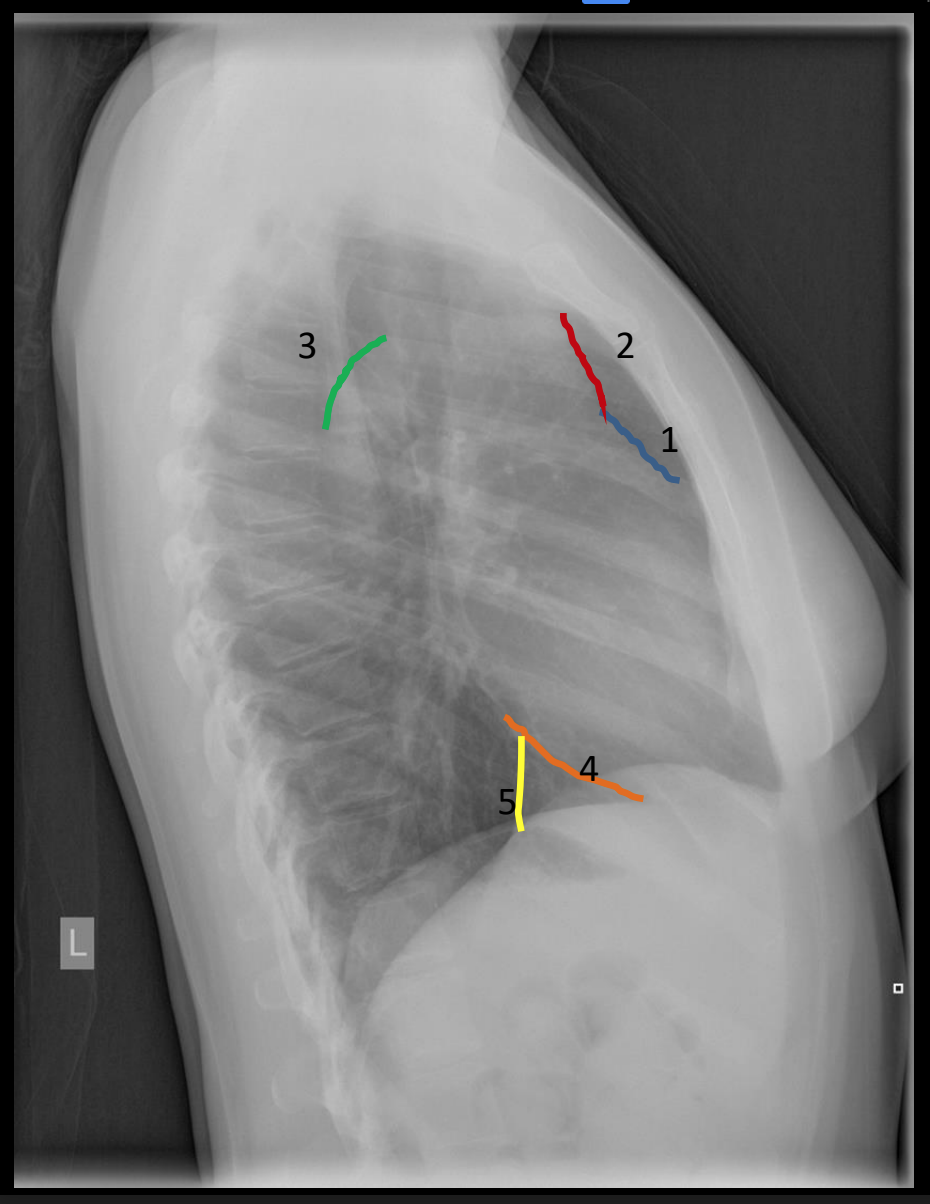

what is 4?

posterior clear space

what is 2?

anterior clear space

what is 7?

spine of left scapula

what is 6?

superior margin of anterior right rib 9

what is 5?

left hemidiaphragm